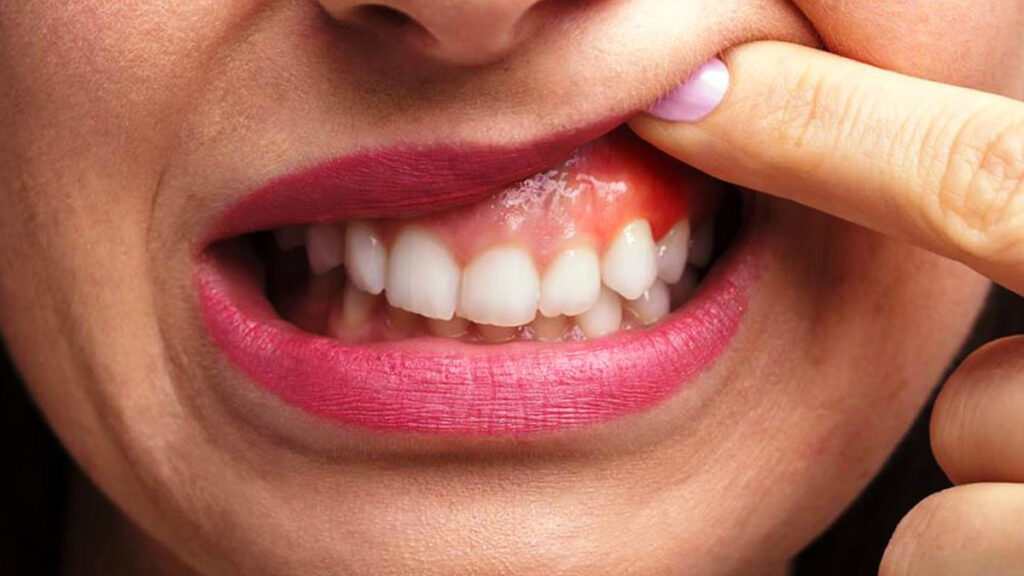

Diş eti estetiği, hem fonksiyonel hem de estetik diş sorunlarını çözme potansiyeline sahiptir. Bu tedavi ile çeşitli diş eti problemleri başarıyla giderilebilir. İstanbul diş eti estetiği, diş etlerindeki renk ve şekil bozukluklarına çözüm sunarak, daha sağlıklı ve estetik bir gülüşe kavuşturur. İşte diş eti estetiği ile düzeltilen başlıca sorunlar:

- Renklenmeler: Özellikle sigara içenlerde görülen diş etlerindeki kahverengi veya daha koyu renklenmeler. Bu, estetik müdahalelerle sağlıklı bir pembeye dönüştürülebilir.

- Diş Eti Şekil Bozuklukları: Diş etlerinin düzensiz şekillerde büyümesi veya çekilmesi gibi durumlar. Estetik prosedürlerle diş etleri yeniden şekillendirilir ve düzeltilir.